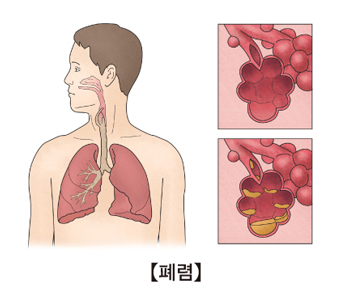

폐렴은 세균이나 바이러스에 의해 세기관지 이하 폐조직에 염증이 발생하는 감염성 질환입니다. 일반적으로 발열, 기침, 가래와 같은 증상이 나타납니다. 흉부 X-ray 사진에서 폐렴을 의심할 수 있는 소견이 확인됩니다.

폐렴의 원인으로는 세균, 바이러스, 곰팡이 등이 있습니다. 드물게는 화학 물질이나 구토물 같은 물질을 흡입함으로써 폐에 염증이 생길 수 있습니다. 요즘은 효과적인 항생제 덕분에 폐렴의 많은 경우가 완치가 되고 있습니다. 하지만 폐렴 원인균의 항생제 내성도 전차 더 강해지고 있어 폐렴은 옛날보다 더 치료하기 어려워졌습니다.

폐렴이 생기면 기침, 가래, 호흡 곤란과 같은 증상이 나타납니다. 특히 가래 색깔이 노랗거나 탁하게 변하는 경우가 많습니다. 발열, 오한이 동반되는 경우가 흔합니다. 하지만 경미한 폐렴의 경우에는 특별한 증상이 나타나지 않을 수 있습니다. 피로감, 두통, 설사와 같은 비특이적인 증상이 발생하는 경우도 있습니다.

폐렴은 증상과 징후 및 배양 검사의 결과를 통해 진단할 수 있습니다. 하지만 각 개인에 따라 증상이 다른 경우가 많습니다. 균 배양이 되면 정확하게 진단이 되지만, 균 배양은 폐렴의 50% 정도에서만 이루어집니다. 정확한 진단을 위해 흉부 방사선 검사를 시행합니다. 객담 검사, 혈액 검사, 혈청 검사, 흉막액 배양 검사 등이 시행되기도 합니다.

폐렴의 치료에서는 주사 혹은 경구 항생제를 투여하는 것이 중요합니다. 증상이 심하지 않다면 외래에서 치료합니다. 호흡 곤란 등 심한 증상이 나타나면 입원 치료를 진행합니다.